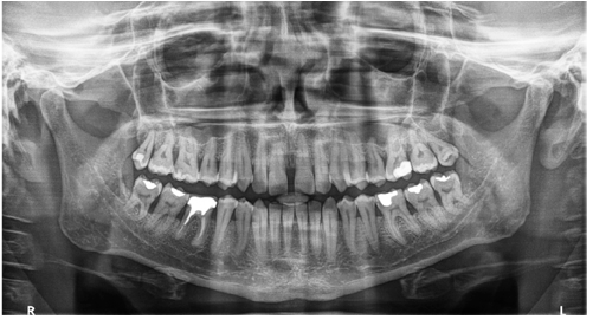

Panorámico

Una gama completa de programas panorámicos cubren todas sus necesidades de rutina, incluidas, entre otras, opciones de aleta de mordida extraoral, FMS extraoral y baja dosis